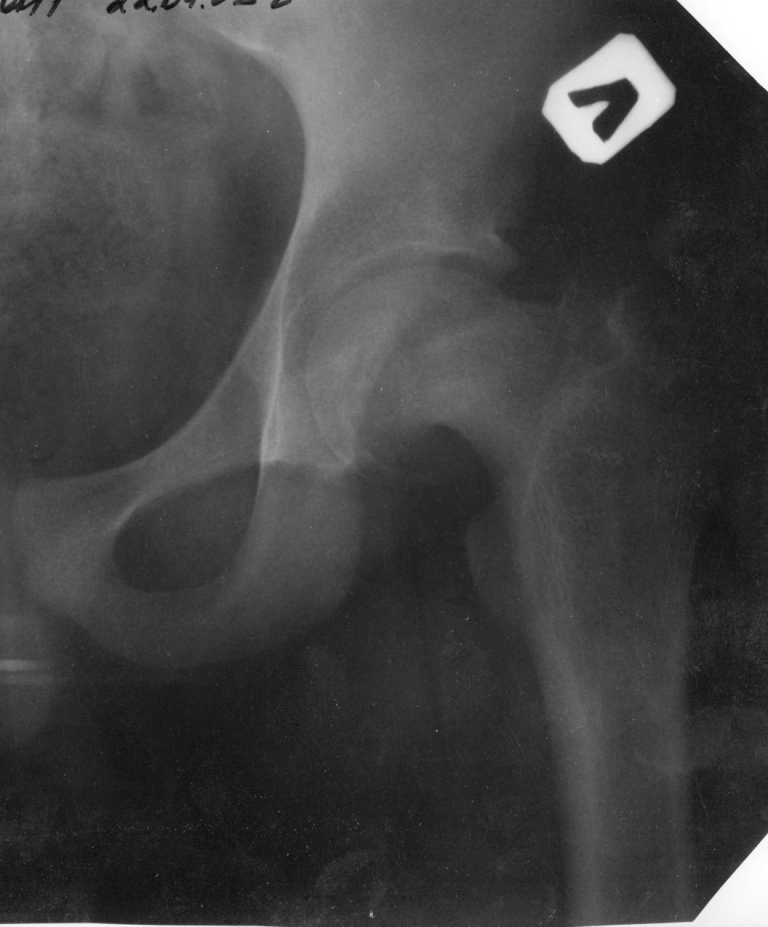

Ребёнок 14 лет. Весом под центнер. Имеющаяся рентгенологическая деформация деформация - на момент поступления. Госпитализирован ребёнок 14 лет. Мальчик, мягко говоря, крупный, гиперстенического типа сложения, ближе к десантнику. Весит 95 кг. Ожирение 2-й степени. Со слов больного - испытывает дискомфорт в области тазобедренного сустава в течение 3-х месяцев. На рентгенограммах - положение дел на момент поступления - конец мая. Укорочение конечности на 1,5 см. Ограничение внутренней ротации. Ходит, едва заметно прихрамывая на больную ногу. Эндокринологический статус находится в стадии обследования. Выполнена рентгенография в стандартных укладках, спиральная КТГ.Ясное дело, головка бедра <ушла> вниз и кзади. Пытающаяся <поймать> её шейка варизировалась и исполнила ретроверсию, создав изгиб во фронтальной плоскости. На рентгеноскопии - подвижность головки не определяется. Мальчик имеет далеко идущие планы на обустройство собственной жизни и образование. Крайне негативно относится к длительной иммобилизации и консервативному лечению. Загодя не согласен со снижением качества жизни в процессе лечения. Мнения коллег относительно дальнейшего лечения разделились. Успешность репозиции головки под наркозом - сомнительная в связи с имеющейся деформацией шейки бедра. Одни склоняются к тактике невмешательства - разгрузка больной конечности, ФЗТ , массаж, и т.д. Предлагают ждать завершения процесса <сползания> головки в условиях полной разгрузки, <тянуть> сустав до эндопротезирования как можно дольше. Другая группа коллег предлагает немедленную стабилизацию головки, что, кажется, правильно. Принимая во внимание анатомическое соотношение головки и шейки бедра, способ остеосинтеза так же вызвал массу споров, не приведших к единому и окончательному мнению. Пока дискуссия остановилась на стабилизации спицами Бека под контролем ЭОП, возможно с применением электродов для проведения электростимуляции слабыми импульсными токами. Техника проведения спиц, однозначно, будет сопряжена с техническими трудностями, обусловленными имеющейся деформацией шейки. Как бы Вы поступили, коллеги, в данной ситуации?Заранее спасибо. И прошу прощения за качество спимков. Буду отправлять их по очереди.

Здравствуйте Данил. По представленным рентгенограммамам и кт срезам Вы имеете дело хронической, стабильной формой ЮЭГБК. Шеечно- эпифизарная деформация выраженная, эпифиз отклонён кзади более чем на 70 градусов, практически до упора в межвертельную ямку, что характеризует её как тяжёлую степень. В выборе метода лечения мы придерживаемся следующей схемы: